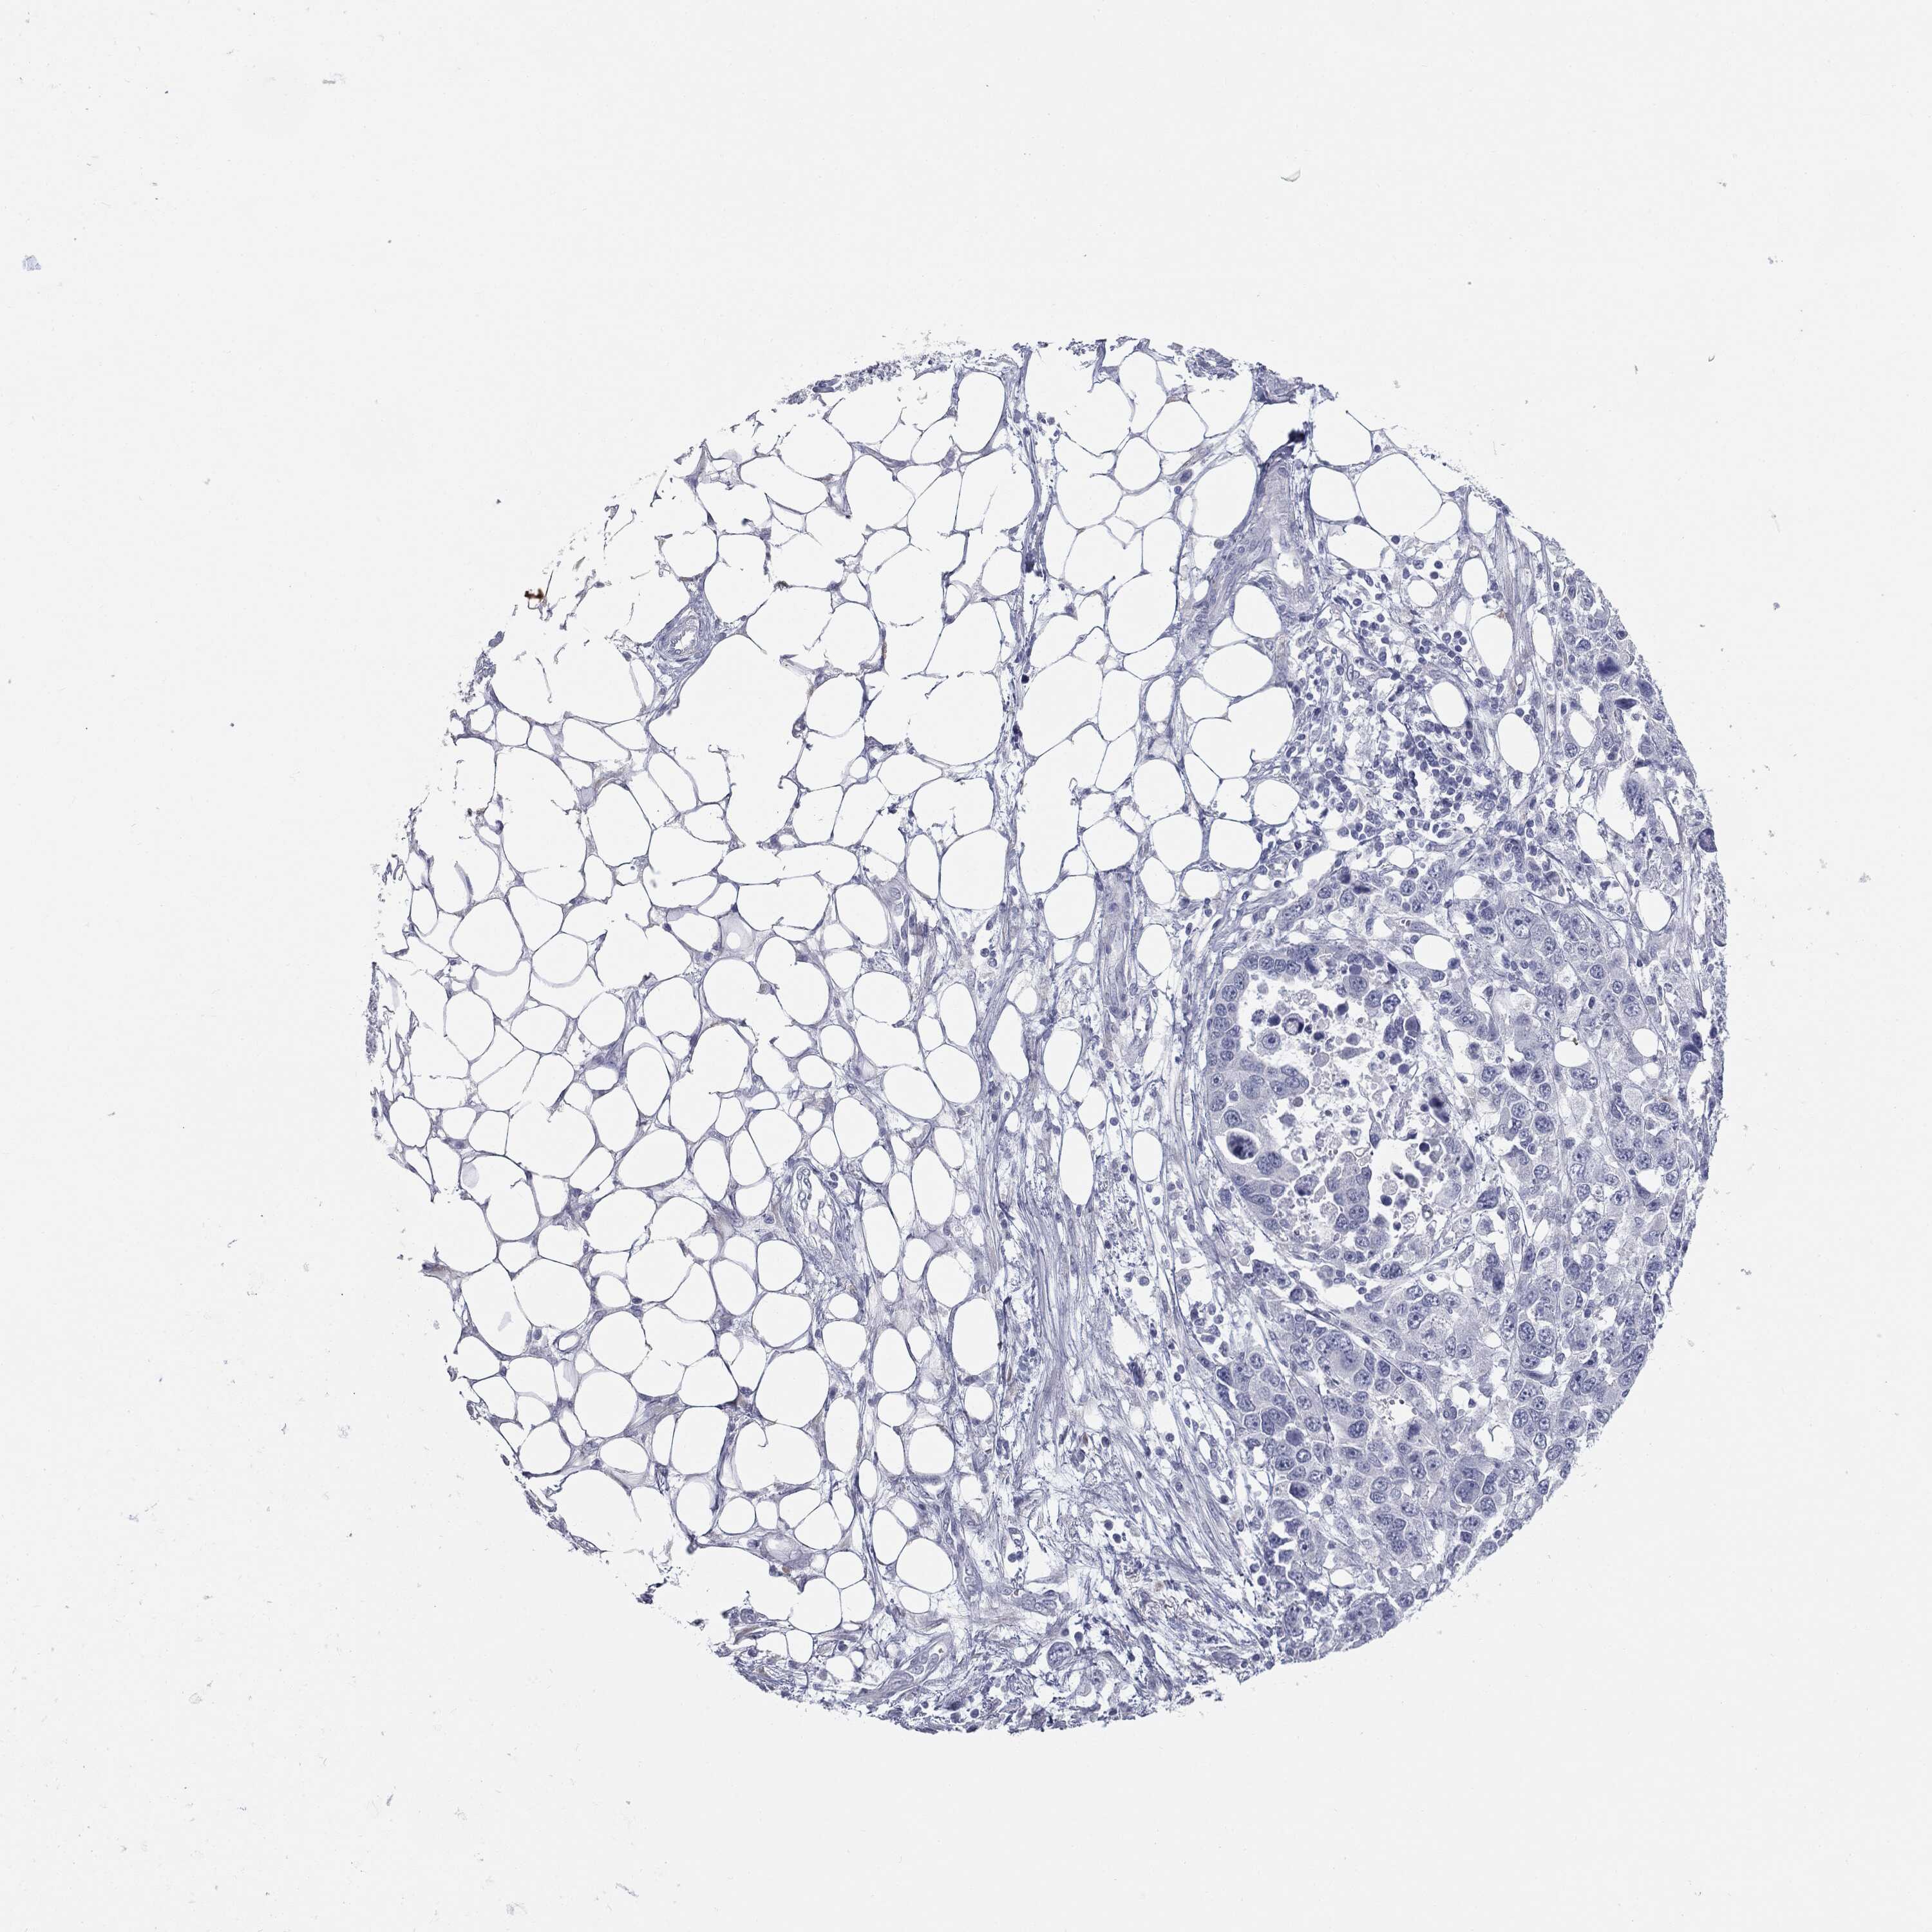

OVARIAN CANCER - Protein expressioni

A mouse-over function shows sample information and annotation data. Click on an image to view it in a full screen mode. Samples can be filtered based on level of antibody staining by selecting one or several of the following categories: high, medium, low and not detected. The assay and annotation is described here.

Note that samples used for immunohistochemistry by the Human Protein Atlas do not correspond to samples in the TCGA dataset.

Antibody stainingi

Antibody staining in the annotated cell types in the current human tissue is reported as not detected, low, medium, or high, based on conventional immunohistochemistry profiling in selected tissues. This score is based on the combination of the staining intensity and fraction of stained cells.

Each image is clickable and will lead to virtual microscopy that enables deeper exploration of all samples and also displays staining intensity scores, fraction scores and subcellular localization as well as patient and tissue information for each sample.

HPA040615

Cystadenocarcinoma, serous, NOS

Carcinoma, endometroid

Cystadenocarcinoma, mucinous, NOS

Carcinoma, NOS